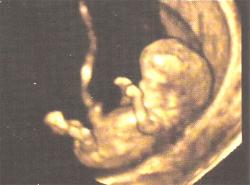

En la actualidad existe un nuevo equipo de última generación que ofrece imágenes del interior del útero tridimensionales y con movimiento, se trata de la cuarta dimensión o ecografía 4D , cuyo principal aporte es el estudio del comportamiento fetal intra útero ya que podemos ver los movimientos fetales, sus gestos y su reacción frente a distintos estímulos.

La ecografía 3D-4D brinda una nueva herramienta para evaluar al feto mejorando la potencialidad diagnostica, ofrece imágenes de alta calidad, pudiendo los padres ver las facciones y gestos de su hijo y según algunos especialistas afianzar de esta forma los vínculos. Otra aplicación de la ecografía 3D-4D en el campo de la obstetricia es en la detección de distintas anomalías fetal, aportando información adicional para el estudio de malformaciones faciales, de extremidades y de columna.

Sin embargo debemos mencionar que las ecografías 3D y 4D tienen ciertas limitaciones en la obtención de las imágenes, dependiendo en primer lugar del tamaño del feto, ya que cuando es muy pequeño no puede ser correctamente apreciado porque solo veríamos sus huesitos, también debe existir una cantidad adecuada de líquido amniótico para que haya contraste y podamos observar el feto con claridad y por ultimo se debe tener en cuenta la posición fetal, sus movimientos y la localización de la placenta.